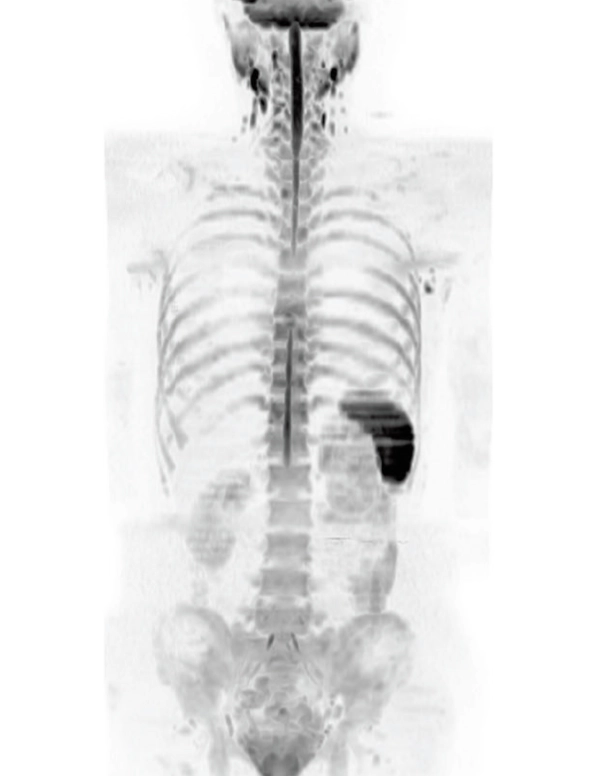

DWI AX (MIP)

3.7×3.1×5.0 mm

3st total scan time 7:25